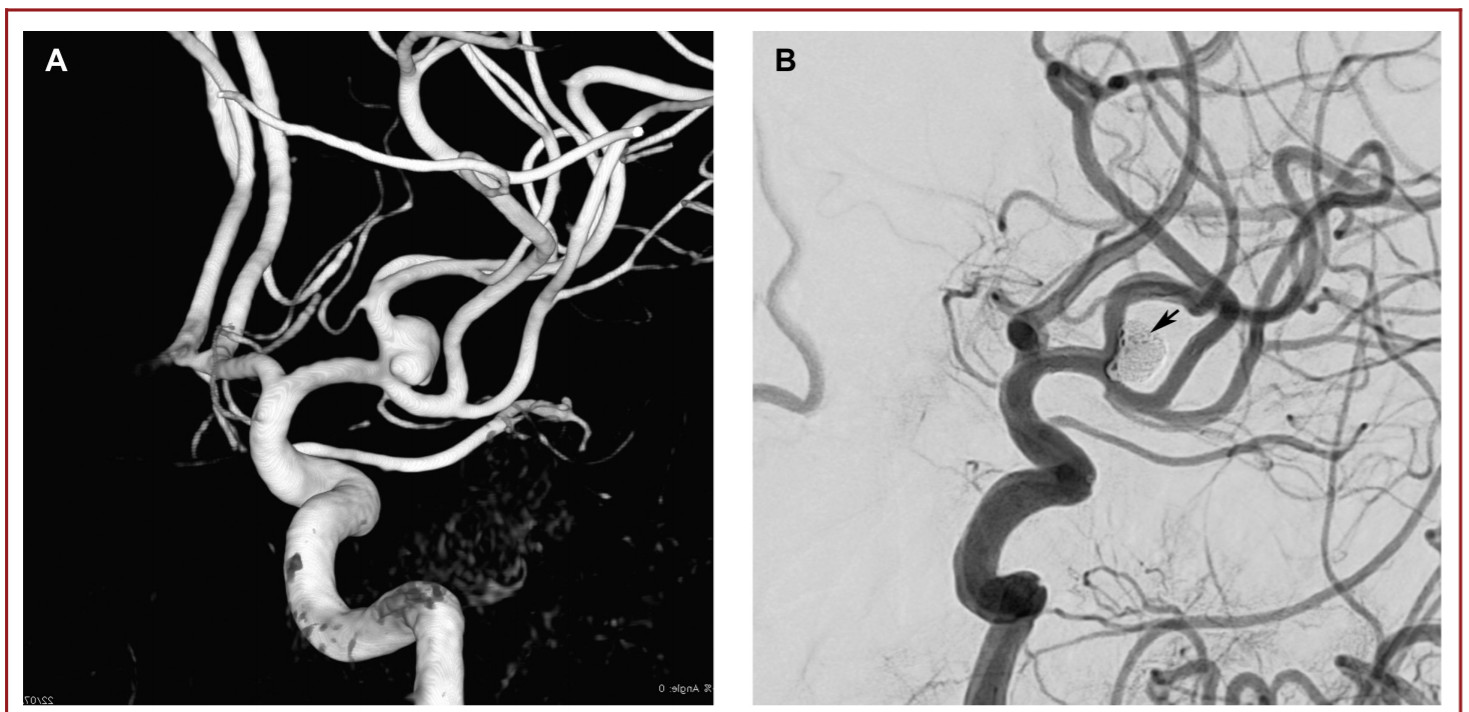

本研究回顾性分析了30例动脉瘤患者(20名女性)(表1)。纳入研究患者的平均年龄为52.4±8.9岁(34-66岁)。动脉瘤的瘤体最大直径为6.9±2.2 mm(4-16 mm)(图1)。分叉侧支的平均直径为2.2±0.3 mm(范围1.6-2.9 mm)。在支架展开或动脉瘤填塞的过程中,无操作相关并发症。术后即刻造影显示RR分级1级,2级,3级的患者例数分别为25例(83.3%),4例(13.3%),1例(3.3%)。无患者死亡,术后即刻神经系统检查较术前无变化。DSA造影随访平均时间为11.8±7.8月(6-36 月)。2名患者(6.7%)发生了围手术期(3.3%)或延迟并发症(3.3%)。上述延迟并发症导致患者永久性致残(3.3%)。全部患者的最终随访DSA结果显示:28例患者达到RR 1级闭塞(93.3%),2例患者实现RR 2级闭塞(6.7%)(表2)。在30例患者中,有28例患者临床随访显示mRS评分为0分。发生延迟性缺血性并发症的患者最终mRS评分为4分。一名术前mRS评分为2的患者术后随访mRS评分没有任何变化。